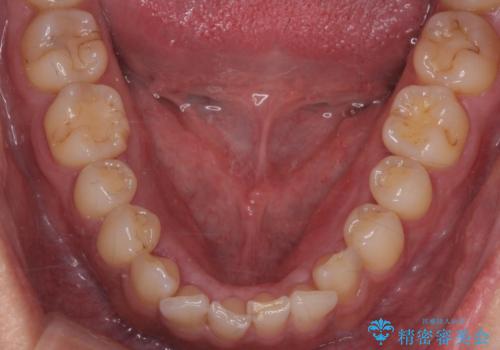

- 下顎の骨隆起を取りたいとのことで来院された患者様です。

右側と左側で2回に分けて行いました。